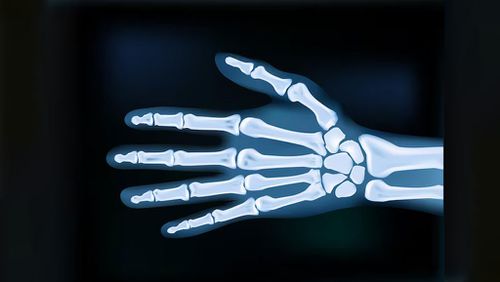

মাইক্রোপ্লাস্টিক এখন এতটাই ছড়িয়ে পড়েছে যে আমরা তা খাচ্ছি, পান করছি আর নিশ্বাসের সঙ্গে টানছি। ফলে এগুলো আমাদের মল, প্লাসেন্টা, প্রজনন অঙ্গ এমনকি মস্তিষ্কেও পাওয়া যাচ্ছে। এবার জীবাশ্ম জ্বালানি থেকে তৈরি পাঁচ মিলিমিটারের চেয়েও ছোট আকারের কণা আমাদের হাড়ের ভেতরে গভীর পর্যন্ত পৌঁছে গেছে।

বিজ্ঞানবিষয়ক সাময়িকী সায়েন্স অ্যালার্ট জানিয়েছে, নতুন এক পর্যালোচনা গবেষণায় ৬২টি পুরোনো গবেষণার ভিত্তিতে বলা হচ্ছে, মাইক্রোপ্লাস্টিক ও আরও ক্ষুদ্র ন্যানো প্লাস্টিক আমাদের কঙ্কাল স্বাস্থ্যে নানা ধরনের প্রভাব ফেলছে। এই পর্যালোচনা গবেষণা প্রকাশিত হয়েছে স্প্রিঙ্গার জার্নালে।

এ বিষয়ে ব্রাজিলের স্টেট ইউনিভার্সিটি অব কাম্পিনাসের চিকিৎসাবিজ্ঞানী রদ্রিগো বুয়েনো দে অলিভেইরা বলেন, ‘এক উল্লেখযোগ্য গবেষণার ফলাফল দেখাচ্ছে যে মাইক্রোপ্লাস্টিক হাড়ের টিস্যুর গভীরে, যেমন অস্থিমজ্জায় পৌঁছে যেতে পারে এবং এর বিপাক প্রক্রিয়ায় ব্যাঘাত ঘটাতে পারে।’

মানুষের ওপর পরিচালিত কিছু গবেষণায় দেখা গেছে, খাবারের মাধ্যমে শরীরে প্রবেশের পর রক্তের সাহায্যে এই প্লাস্টিকের অবশিষ্টাংশ হাড়ের টিস্যুতে জমা হচ্ছে। প্রাণীর শরীরে করা গবেষণায় দেখা গেছে, এগুলো হাড়ের বৃদ্ধি কমিয়ে দেয়। পাশাপাশি হাড়ের বৃদ্ধি ও মেরামতে সাহায্যকারী অস্টিওক্লাস্ট কোষের কাজ ব্যাহত হয় এর ফলে। এতে হাড় দুর্বল হয়ে পড়ে, বিকৃত বা ভেঙে যাওয়ার ঝুঁকিও বেড়ে যায়।